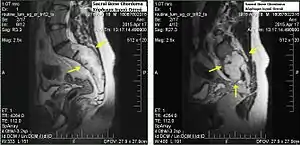

.jpg.webp)

Chordomas can arise from bone in the skull base and anywhere along the spine. The two most common locations are cranially at the clivus and in the sacrum at the bottom of the spine.[2]

Sacral chordoma is presented with chronic low back pain.[3]